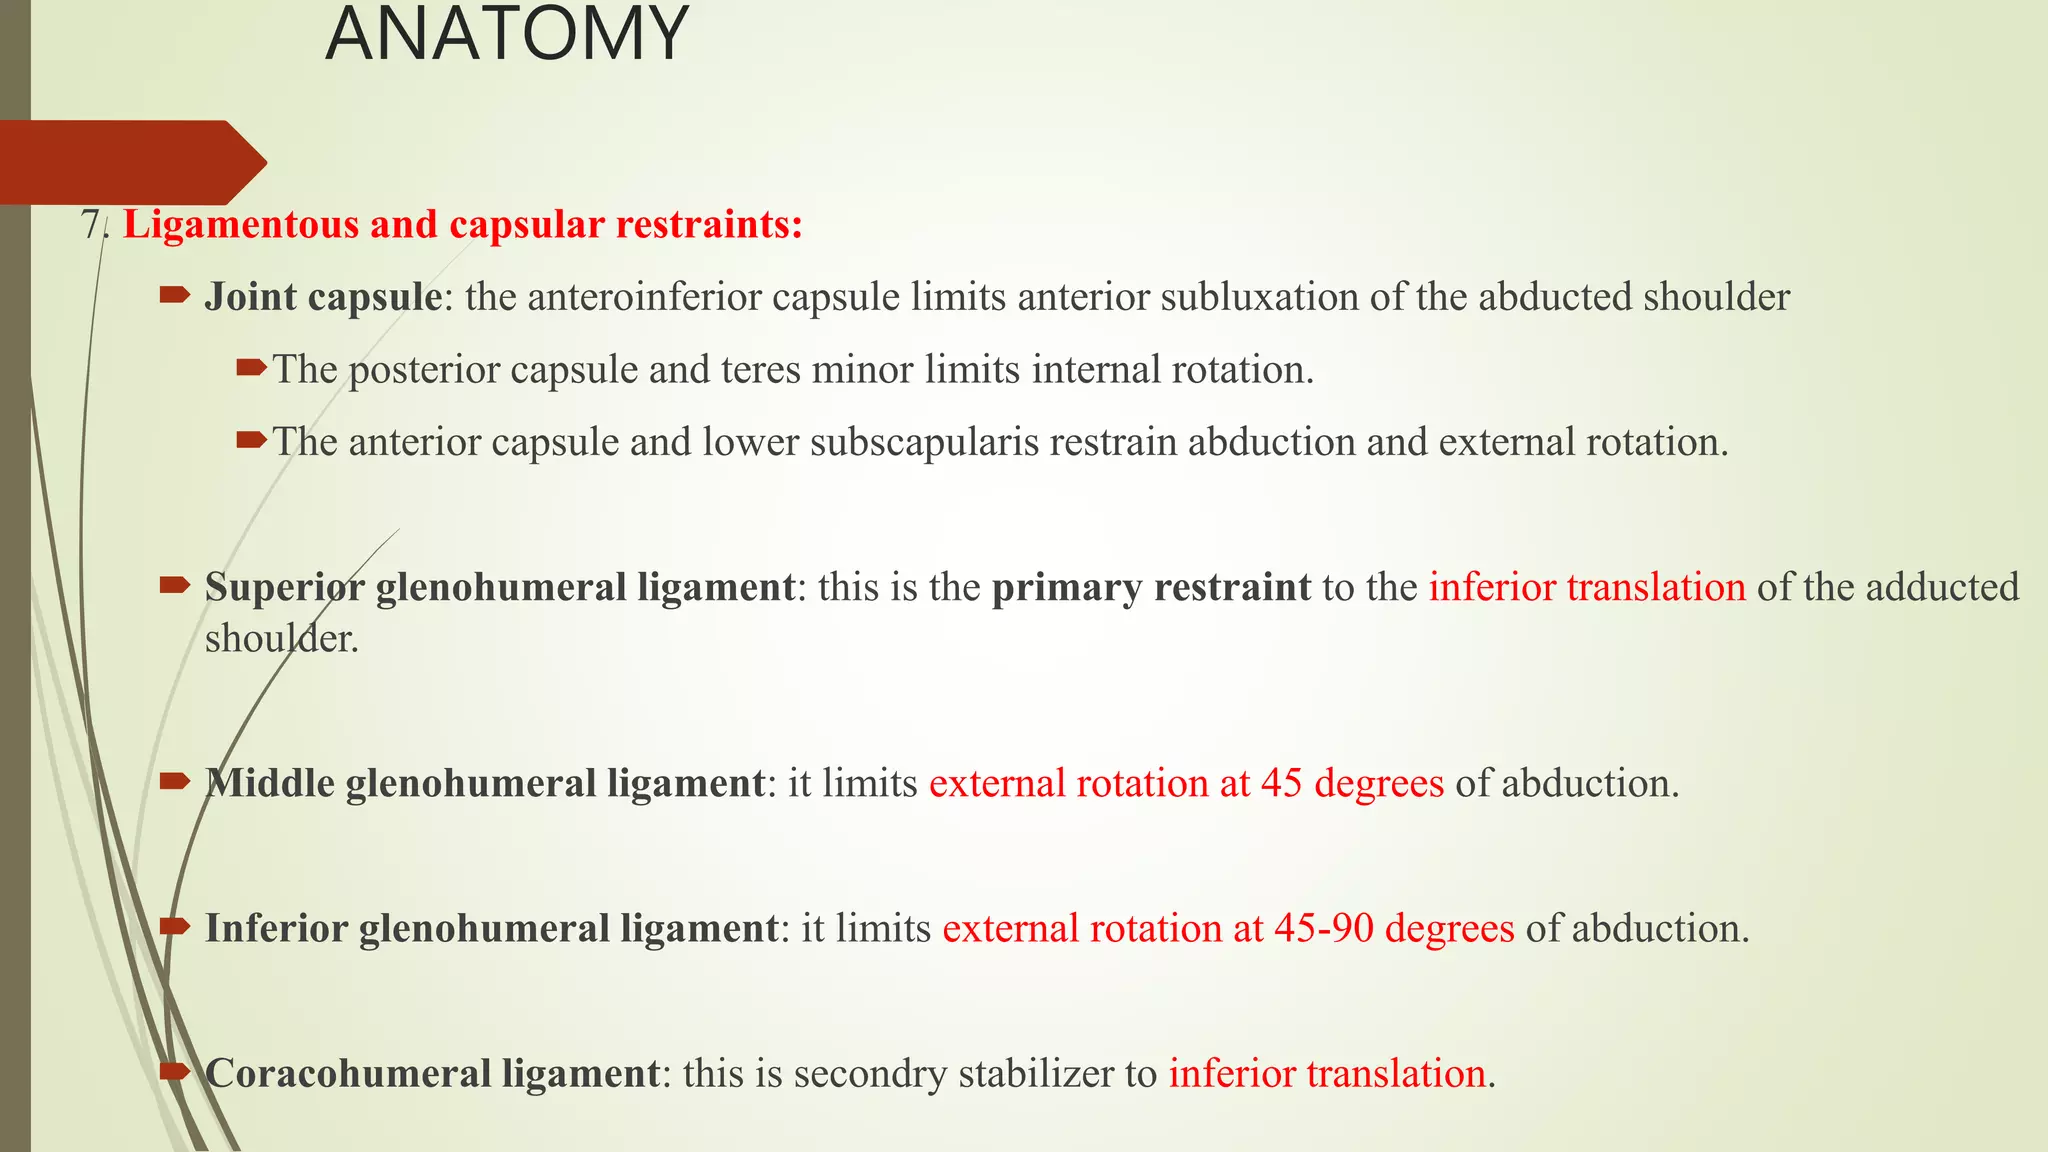

- The shoulder joint is inherently unstable due to its anatomy, relying on both passive structures like the labrum and ligaments as well as active stabilizers like muscles.